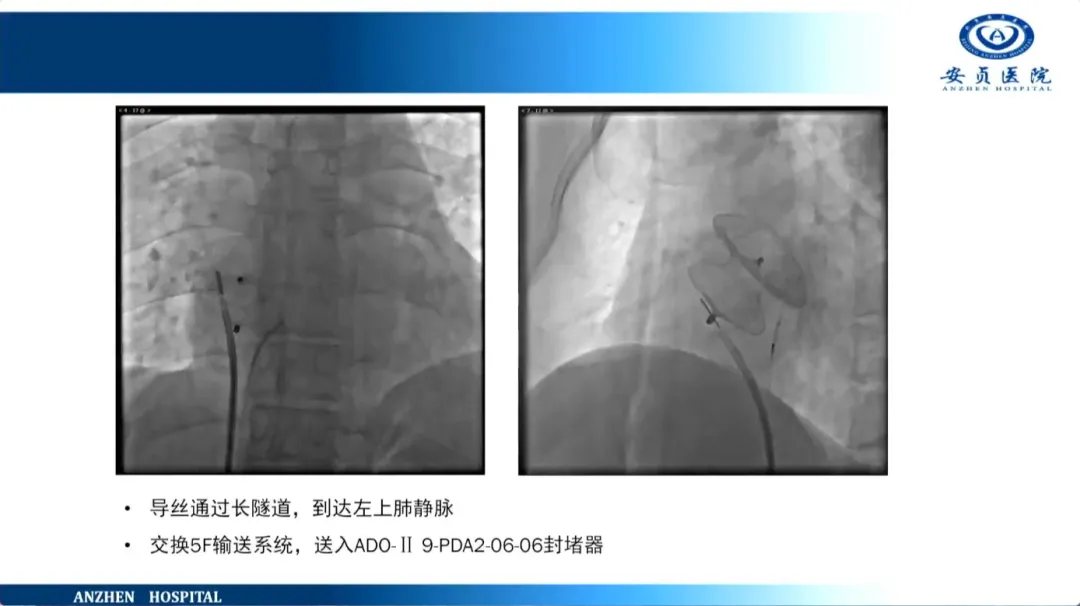

任伟:先心病介入治疗病例分享(29P)